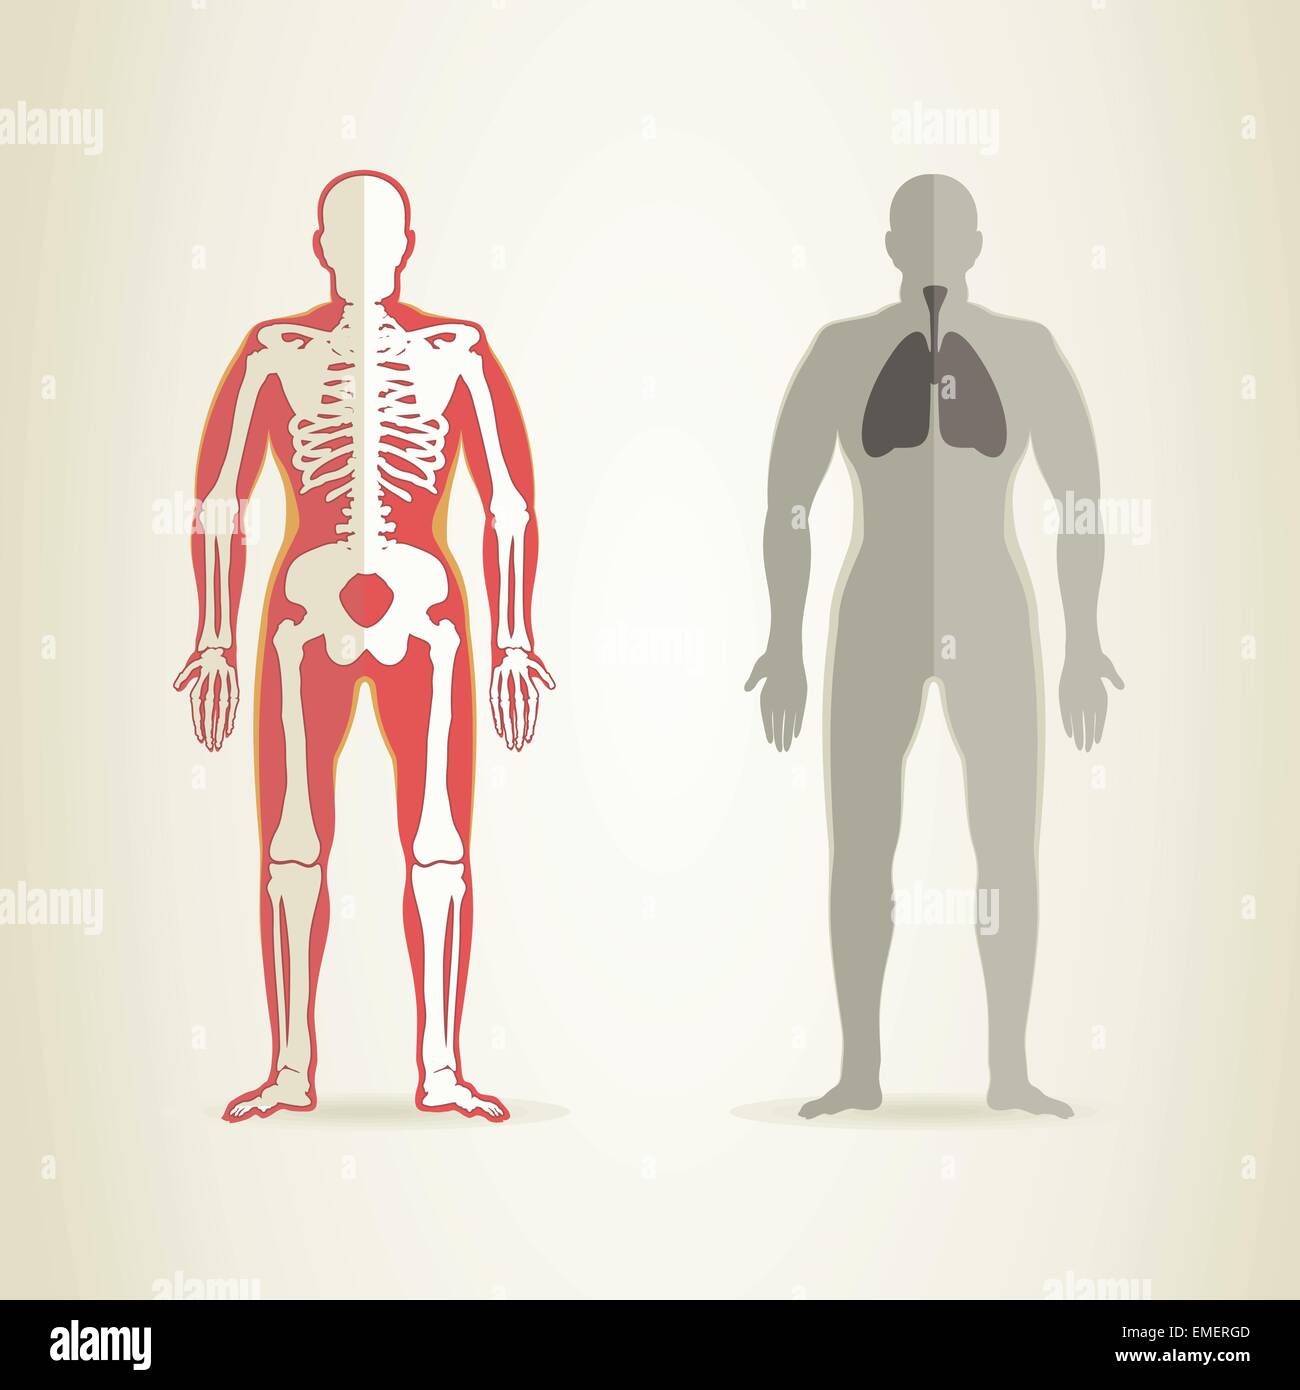

RFRN1RN9–Ensemble de 15 icônes anatomie gris des parties du corps humain, de l'éducation et de la formation médicale, y compris le cerveau, le coeur, le tube digestif, de la colonne vertébrale, et les poumons